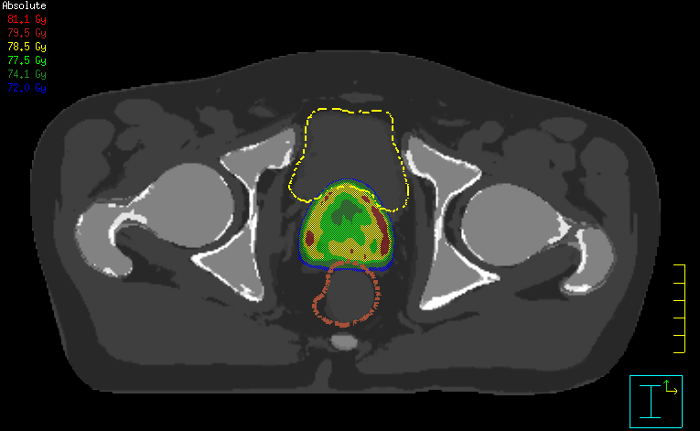

Innovative strategies in MRI-only simulation have made it possible to derive CT-like electron density information from MR imaging data. This capability enables physicians to use MRI as the radiotherapy department’s primary imaging modality for specific applications to eliminate tedious and error-prone CT-MR registration and simplify workflows.

Clinicians at Finland’s Turku University Hospital have streamlined their workflow for prostate cancer radiotherapy with MR-only simulation.